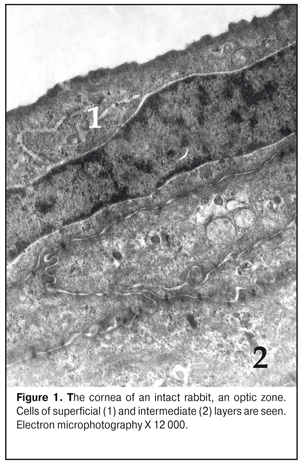

https://doi.org/10.31288/oftalmolzh201736369 Effect of colloidal silver nanoparticle solution instillation on the ultrastructure of the corneal epithelium and stroma V.A. Ulyanov, Prof., Dr. Sc. (Med.) 1 M.B. Makarova, a Postgraduate student, immunologist1, 2 N.I. Molchaniuk, Cand. Sc. (Biol.) 2 N.A. Ulyanova, Prof., Dr. Sc. (Med.) 1 V.M. Skobeeva, Cand. Sc. (Phys.-Math.) 3 E.A. Chernezhenko, a junior research fellow 2 1 Odessa National Medical University; 2 Filatov Institute of Eye Diseases and Tissue Therapy 3 Mechnikov Odessa National University Odessa, Ukraine E-mail: makarovambdoc@mail.ru Introduction. Existing methods of treatment for bacterial keratitis do not always provide a positive therapeutic effect and do not prevent the occurrence of relapses. The main reason for this is the development of resistance of microorganisms to antibiotics. The use of silver nanoparticles with antimicrobial properties may be promising in the treatment of bacterial keratitis. However, the effect of silver nanoparticles on the structure of the cornea has not been adequately studied. Objective: to study the effect of instillations of a colloidal solution of silver nanoparticles measuring 30 nm on the ultrastructure of the epithelium and stroma of the rabbit's cornea. Material and Methods. The colloidal solution of silver nanoparticles 30 nm in size was instilled into the conjunctival cavity of rabbits three times a day. Ultrastructural changes in epithelial cells and corneal stroma, changes in connective tissue plates and collagen fibrils of the stroma were evaluated at Days 15 and 30 of the experiment. Results. The effect of silver nanoparticles caused an increase in the number of ribosomes in the superficial cells of the corneal epithelium, hydrophilic changes in membrane organelles, an increase in the number of ribosomes in all cells of the basal layer, and destruction of individual organelles in single cells. In the stroma, the edema of the main substance was observed; the areas of defibration, homogenization or fragmentation of collagen fibril bundles were determined. The dystrophic changes were more severe as the duration of instillations of silver nanoparticles increased. Conclusions. The daily instillations of the colloidal solution of silver nanoparticles measuring 30 nm in the conjunctival cavity in the course of 15 and 30 days caused the dystrophic changes in the superficial and basal cells of the corneal epithelium. In the stroma of the cornea, the dystrophic changes in keratocytes, violation of the architectonics of connective tissue plates, defibration and fragmentation of collagen fibrils were detected. Key words: corneal ultrastructure of the epithelium and stroma, silver nanoparticles, experiment Background Treatment of bacterial keratitis is one of the current issues in ophthalmology today. The disease is characterized by a severe clinical course which leads to vision impairment as well as to complication development [1]. Existing methods of treatment for bacterial keratitis do not always provide a positive therapeutic effect and do not prevent the occurrence of relapses [2]. The main reason for this is the development of resistance of microorganisms to antibiotics, resulting in appearance of superstrains and disbacteriosis development. However, colloidal solutions of silver nanoparticles, which have an anti-microbial effect, in a form of Collargol and Protargol drugs are actively used in ophthalmology. The drugs pointed are products of compounds of colloidal (metallic) silver with protein. Bacterial keratitis pathogenesis is a complicated process involving the interaction of many local and general factors (hormonal, paracrine, nervous, vascular, and cellular ones) [3]. In this regard, a further search for therapeutic agents than could be used in keratitis treatment is required. Today, investigations on the effect of silver nanoparticles (AgNPs) on the local ocular immunity which plays an important role in the inflammation course are of a special scientific and practical interest [4]. AgNP application is promising in bacterial infections complicated by biofilm formation. AgNPs have been noted to have an immune-modulating action; it has been determined that silver is able both to stimulate and to inhibit a neutrophil phagocytic activity in dependence on a doze and a size of silver nanoparticles [5]. AgNPs have anti-microbial and anti-inflammatory characteristics [6]. However, taking into consideration such a small size and high penetrability of AgNPs, not all authors share the opinion that they are completely safe for the medical application [7, 8, 9]. So, this requires the further studying AgNPs in regard of their application efficacy and safety [10], in particular, in keratitis treatment. Purpose: to study the effect of instillations of the colloidal solution of silver nanoparticles measuring 30 nm on the ultrastructure of the corneal epithelium and stroma in rabbits. Material and Methods The study was performed at vivarium of Filatov Institute of Eye Diseases and Tissue Therapy. All experiments followed the bioethical principles stated in the Declaration of Helsinki and the Law of Ukraine On Animal Protection from Cruelty (No 1759-VI dated 15.12.2009) and recommendations of V.D. Mishalova et al. for scientific morphological research [11]. A design of the experiment Groups of the animals studied were: 1) Control group, six intact Chinchilla rabbits which were conjunctivally instilled a normal saline solution; 2) Study group, sixteen Chinchilla rabbits which were conjunctivally instilled a colloidal solution of silver nanoparticles sized 30 nm. Instillations were performed three times a day. The animals were sacrificed by air embolism under thiopental anesthesia at Days 15 and 30 of instillations. Then, eyeball fragments were obtained for morphological examinations. Silver nanoparticles of a spherical shape and 30 nm in size were synthesized by a citrate method at Physics Research Institute of Odessa Mechnikov National University [12]. We used colloidal AgNP solutions with concentration of 0.2 mg/ml. To perform electron microscopy examinations, the corneal tissue samples were fixed in a 2.5% glutaraldehyde solution in phosphate buffered saline (pH 7.4) and postfixed in a 1% osmic acid solution with the same pH of the buffered solution. Afterwards, the samples were dehydrated using a series of increasingly concentrated spirits. The samples were infiltrated and embedded using the Epon-Araldite mixture. Then, the ultrathin sections were contrasted by the method of Reynolds [13]. The sections were examined and imaged using a PEM-100-01 electron microscope. We evaluated ultrastructural changes in epithelial cells of the corneal epithelium, in cells and fibers of the corneal stroma in the central part and in the limbus area. The examinations of the corneal ultrastructure were performed by an Electron Microscopy group of Electron Microscopy and Pathological Morphology Laboratory at Filatov Institute of Eye Diseases and Tissue Therapy. Results and Discussion The ultrastructure of the cornea in the rabbits of Control group The ultrastructure of the cornea in the central part and the limbus area was without pathological changes. Superficial cells of the corneal epithelium had moderate electron-dense cytoplasm in which were placed cisterns of the granular endoplasmic reticulum, numerous free ribosomes, single mitochondria, tonofilaments, a big rod form nucleus (Fig. 1). Single narrow intracellular clefts were detected. Wing cells in the intermediate layer of the corneal epithelium had a typical structure. In the cells, the nucleus was well-defined with sulcate karyolemma; a small electron-transparent rim around the nucleus was noted. Nucleus chromatin was in a dispersed condition. In the cytoplasm, there were diffusely spread a great number of free ribosomes, separated cisterns of the granular endoplasmic reticulum, rare mitochondria. The cells of the superficial and intermediate layers of the corneal epithelium were connected by means of desmosomes and locking plates. Basal cells were placed on the well-defined basal membrane. In the cytoplasm was detected a big nucleous with karyolemma invagination that contained the nucleolus and standard organelles. An electron-dense narrow rim was noted only around the nucleus. In some cells, we detected radiolucency of the intramitochondrial matrix and focal destruction of mitochondrial cristae. The basal membrane of the epithelium, the corneal stroma had no pathological changes (Figure 2).